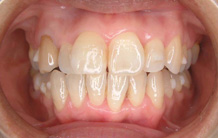

正面から観たところです。

全て乳歯です。反対咬合です。まだ幼児なので、お子様にかかる負担などをよく考えた上で、治療します。

反対咬合です。